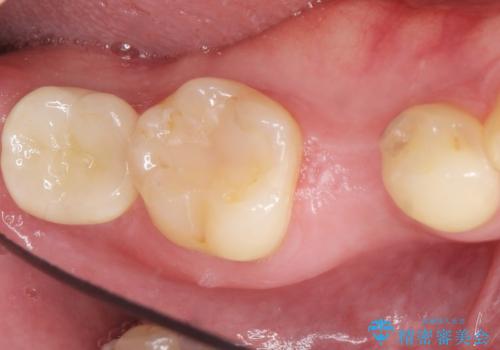

予算を抑えてしっかりとしたインプラント治療 30代男性

- 30代男性

- 奥歯(右下5)のインプラントをご希望し来院された患者様です。

なるべく低予算でとのご希望により、アルファタイトインプラント(保証期間:3年)による治療を行いました。